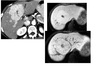

Eosinophilic oesophagitis

Barium - Concentric, ring-like strictures of oesophagus

**Not transient - Permanent **

DDx

feline oesophagus

- folds1-2 mm thick and run horizontally around the entire circumference of the esophageal lumen.

- The findings are transient, seen following reflux and not during swallowing.

- Associated with GORD

- distal two-thirds of the thoracic esophagus